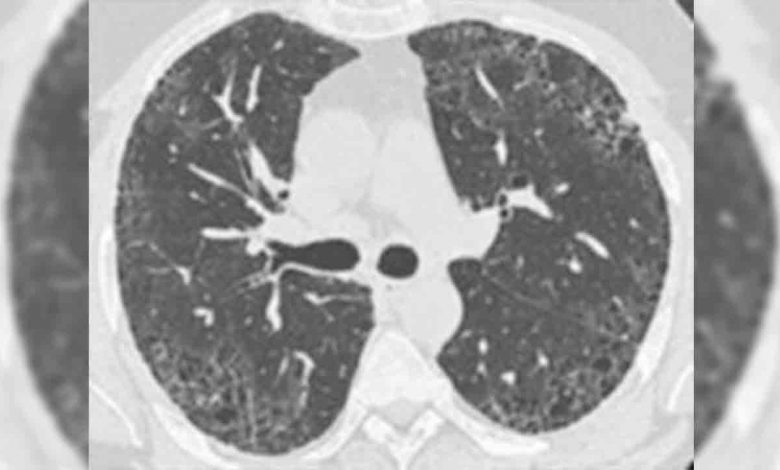

Prof. Dr. Nilgün Yılmaz Demirci, her 100 bin kişiden 14 ila 43 kişiyi etkilediği düşünülen ve dünyada toplam yaklaşık 3 milyon kişiyi etkilediği tahmin edilen bu hastalık hakkında şu bilgileri verdi: “Normal akciğer dokusunun çeşitli sebeplerle oluşan hasarına bağlı olarak kalınlaşıp sertleşmesi ve esnekliğini kaybetmesine akciğer sertleşmesi- pulmoner fibrozis denir. Akciğer sertleşmesi olan hastalarda yaşam süresi kısaldığından tanı ve tedavi süreci doğru şekilde yönetilmeli. Bunun için de hastaların akciğer sertleşmesi konusunda deneyimli bir göğüs hastalıkları uzmanı önderliğinde romatoloji, göğüs cerrahisi, radyoloji uzmanlarından oluşan multidisipliner ekip tarafından değerlendirilmesi önemli. 200’den fazla hastalık akciğer sertleşmesine neden olabilse de çoğunlukla bu hastalığa sebep bulunamayabilir ve bu durum idiyopatik (nedeni bilinemeyen akciğer sertleşmesi ya da pulmoner fibrozis) olarak adlandırılır. IPF ise, akciğer sertleşmesinin en sık görülen çeşididir.”

Demirci, pulmoner fibrozisin tanısal sürecinde tüm aşamaların eksiksiz yapılabilmesinin önemine dikkat çekerek, şu çağrıyı yaptı: “Uyum içinde çalışan multidisipliner ekiplerin olduğu merkez sayılarının artması önemli. Eğer bu merkezler artarsa, akciğer sertleşmesi hastalarının doğru tanı süreci kolaylaşır. Akciğer sertleşmesi tanı ve takibinde ayrıntılı solunum fonksiyon testleri, tekniğine uygun çekilen akciğer bilgisayarlı tomografisi ve romatolojik kan tahlilleri gerekir. Bunları doğru yapılabilen merkezlerin yaygınlaştırılması şart. Akciğer sertleşmesinde tedavi süreci sigaranın bırakılması, sertleşmeyi yavaşlatmaya yönelik- antifibrotik ilaçlar olan pirfenidon ve nintedanib kullanımı, oksijen tedavisi, pulmoner rehabilitasyon, aşılama, akciğer nakli ve yeni ilaç çalışmalarına hastaların yönlendirilmesi gibi çok yönlü bir süreci kapsar. Pulmoner rehabilitasyon ve akciğer nakli yapan merkezlerin yaygınlaştırılmasıyla akciğer sertleşmesi bulunan hastaların bu imkanlara rahatlıkla ulaşabilmesi sağlanabilir.”

BELİRTİLERİ; NEFES DARLIĞI VE ÇITIRTI SESİ